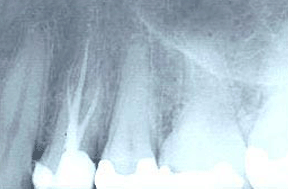

根管治療術前,可見原來的補物下的繼發齲(白色箭頭),黃色箭頭所指是根管內的牙神經。

這是根管治療以后所拍攝的X光片,可見該第一前磨牙有三個根管,并且都已經嚴密的充填了。經過這樣的治療,這顆牙仍然能夠長時間的行使正常功能。當然,應該在該牙外再做一個牙冠, 加以保護,防止折裂。